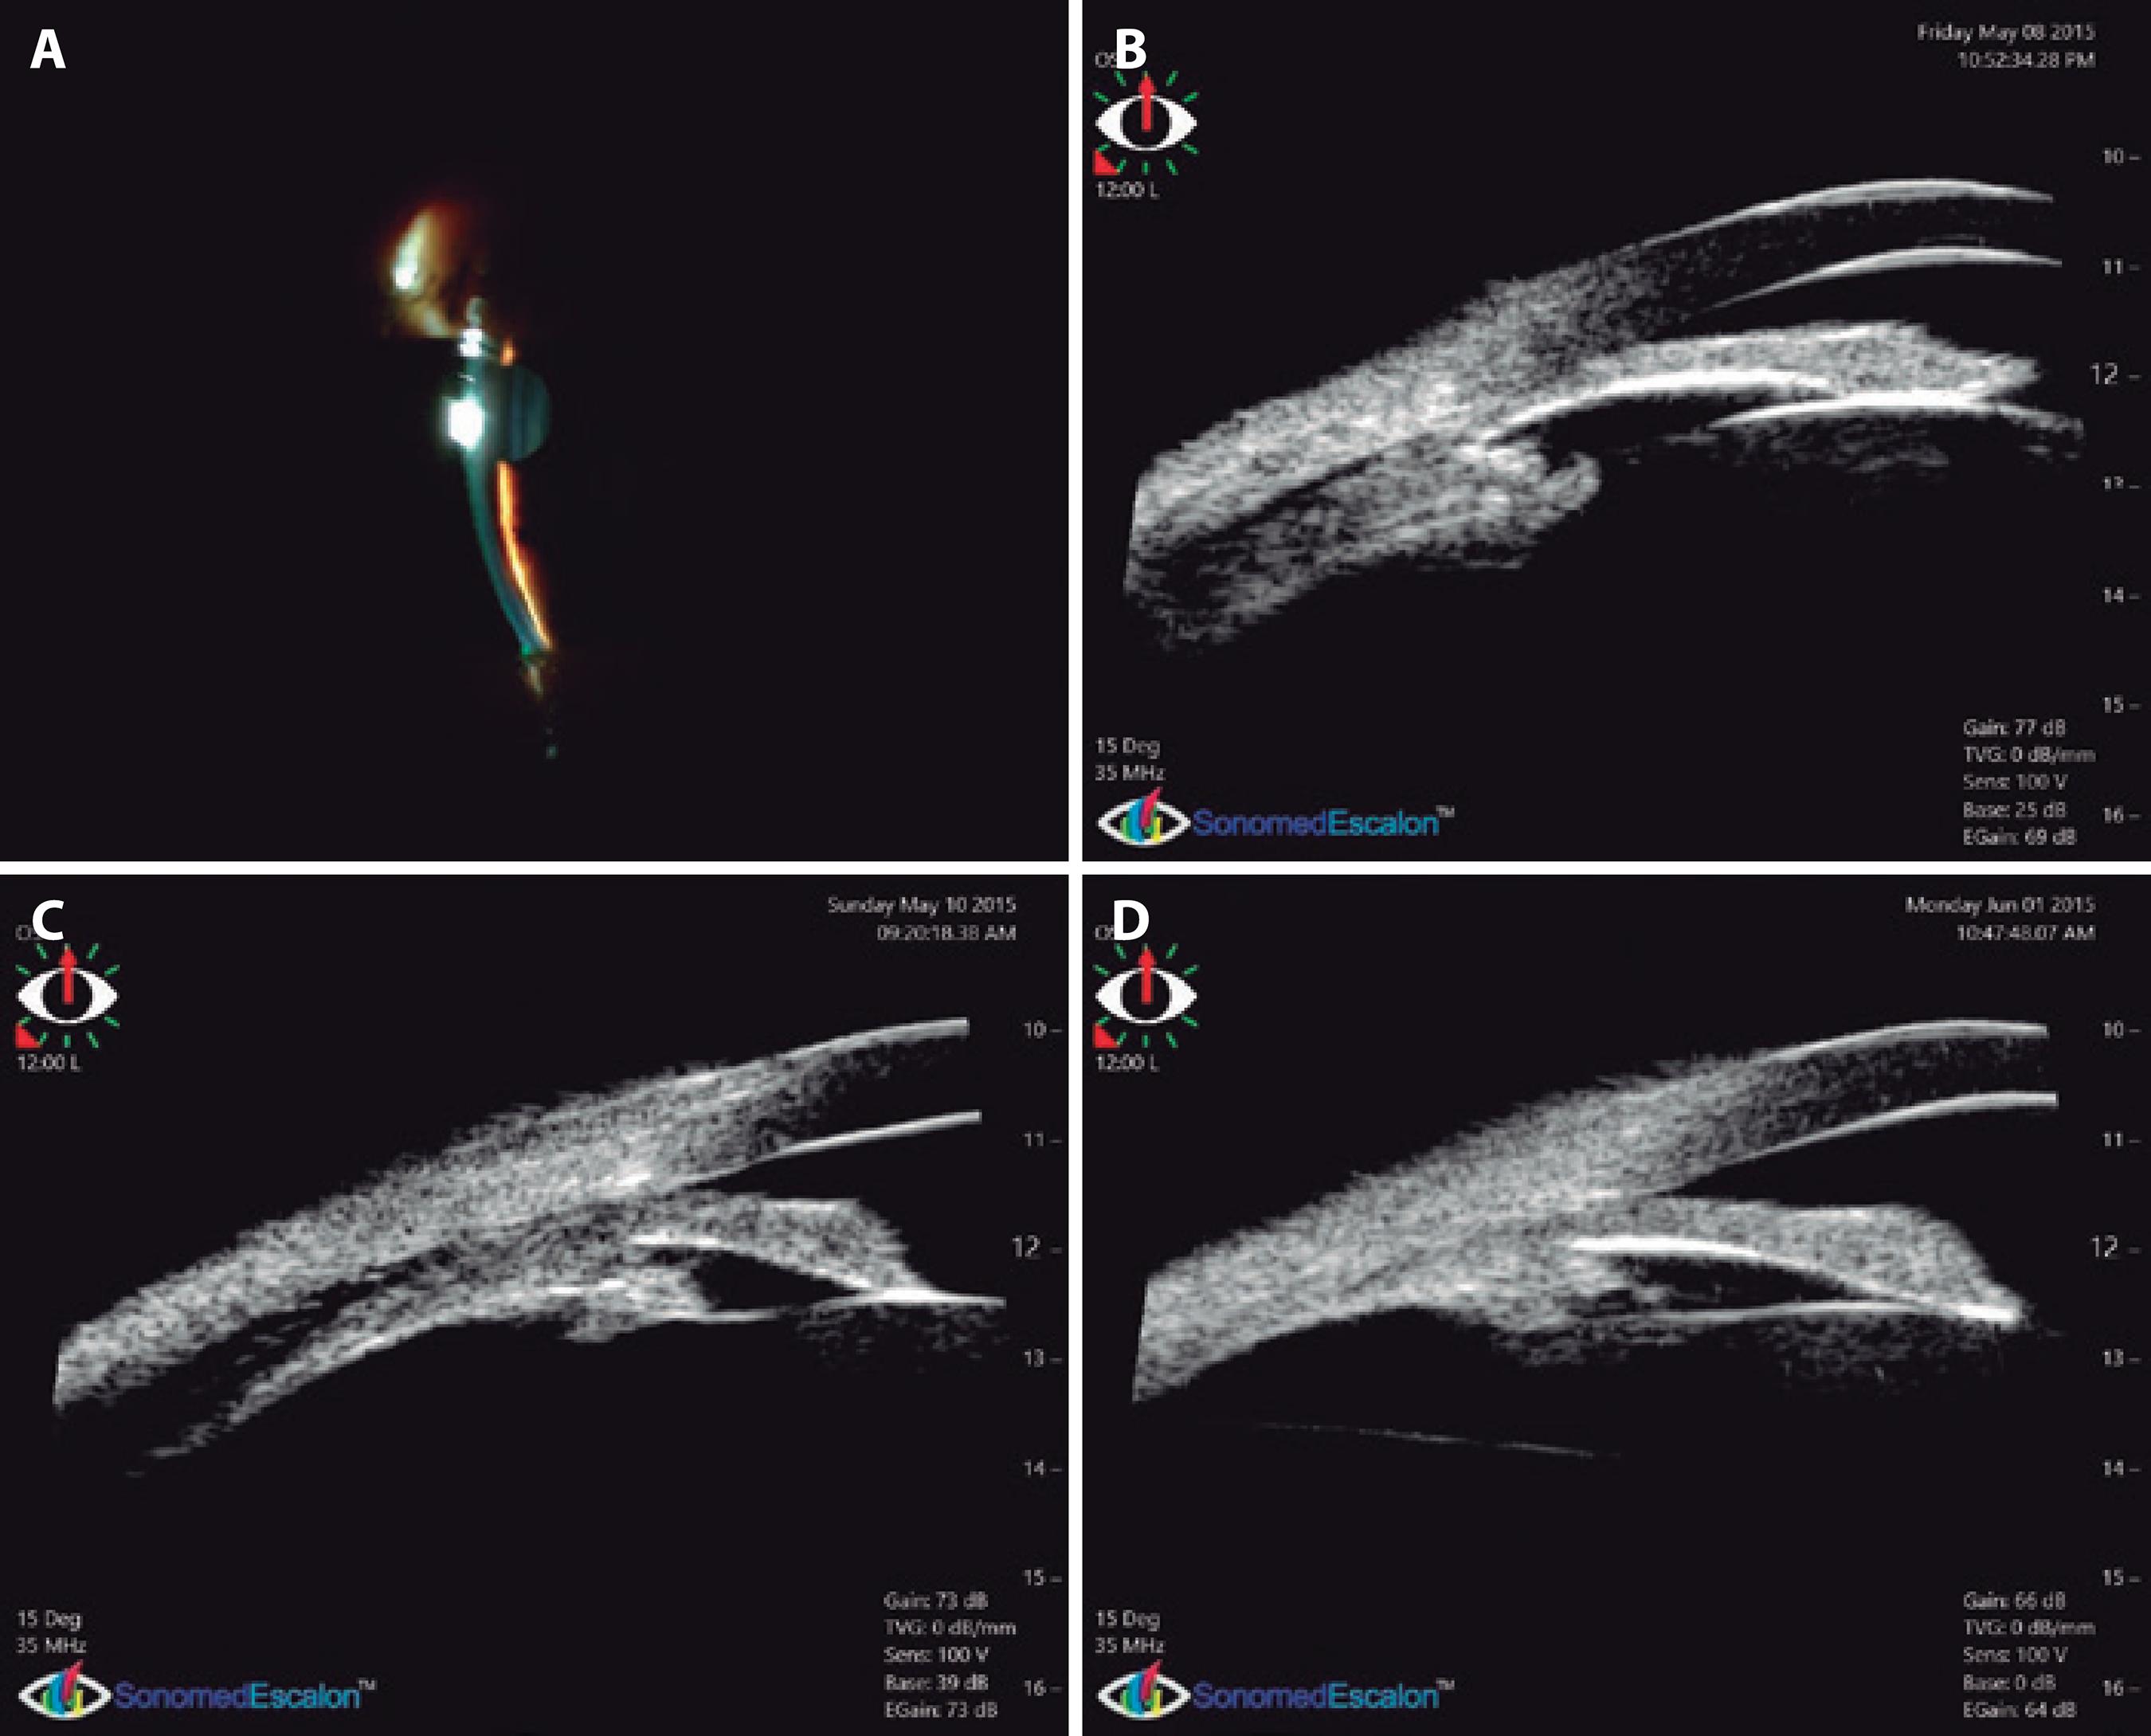

Figure 2 (OS) First day: shallow central and peripheral anterior chamber (A) and UBM showing ciliary detachment and anterior rotation provoking complete iridocorneal apposition (B). Thirty-six hours later: widened angle with mydriatic pupils caused by cycloplegia. Ciliary detachment persists (C). Three weeks later: reattached ciliary body. Angle is wider but still narrow, and with a relative pupillary block configuration (D). All UBM images shown here are from the superior quadrant.

Immersion UBM with a 35-MHz probe (Figures 1 and 2, B) showed bilateral ciliary body effusion and anterior chamber flattening with complete appositional angle closure in all quadrants, which was more evident in OD. Iris contact was complete in OD, whereas OS showed a pupillary block mechanism, with the ciliary body anteriorly rotated to a lesser extent.

Thirty-six hours later, the anterior chamber and angle had widened, but UBM demonstrated continued ciliary effusion (Figures 1 and 2, C). A conventional ultrasound exam was performed, which showed a shallow peripheral uveal detachment and the presence of vitreous hyperreflectivity consistent with vitritis. The patient went on a trip overseas and continued her medication.

Three weeks later, upon returning, her VA was 20/20 OU corrected with +1.50, and slit-lamp examination showed OU with a wider anterior chamber, IOP of 12 mmHg, and normal ocular fundus. The results from UBM were consistent with these findings, showing a widened anterior chamber angle and complete resolution of the ciliary effusion (Figures 1 and 2, D). Nevertheless, the anterior chamber angle remained occludable, with a relative pupillary block configuration. Therefore, a bilateral laser peripheral iridotomy was indicated; at this point, steroid and cycloplegic drops were no longer being used by the patient.